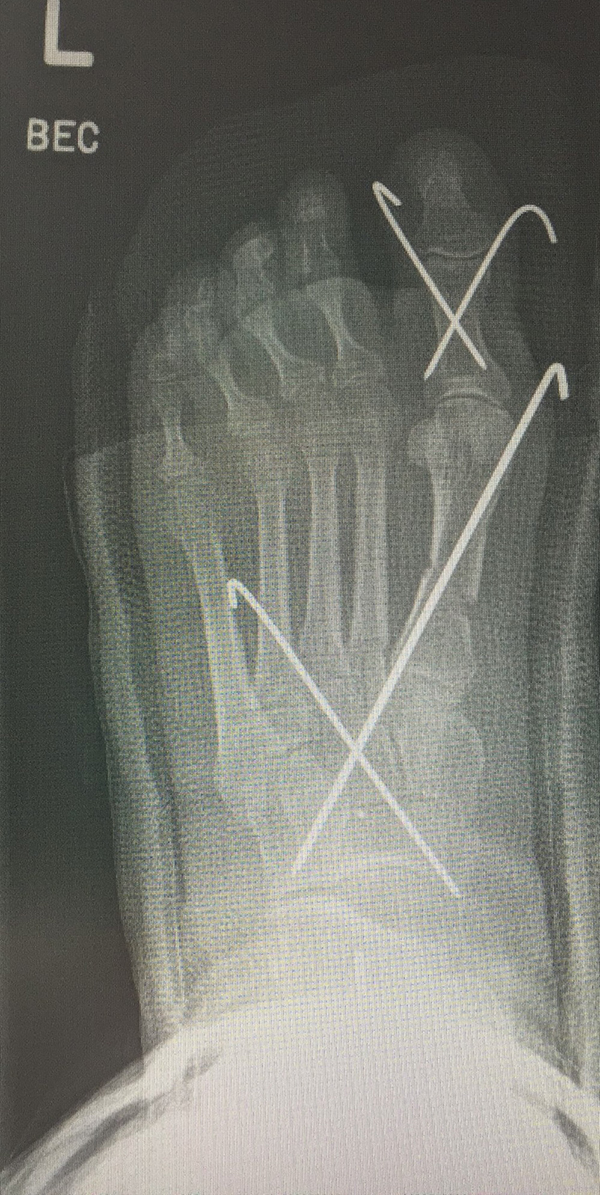

Zusätzlich schränken Wachstumsfugen die Wahl der Osteosynthese ein. Eine die Fuge kreuzende Osteosynthese ist ausschließlich mit Kirschner-Drähten möglich (Abb. 3).

Abb. 3 a-j: Beispiel einer Calcaneusverschiebeosteotomie mit offenen Wachstumsfugen und der entsprechenden Osteosynthese mit Kirschner Drähten. Lokalisation der Osteotomie (a), Lage der Fräse (b-d), Drahtlage mehrere Ansichten (e-h), Heilung der Osteotomie 4 Wochen postoperativ und Entfernung der Drähte (i-j).

Calcaneus-Osteotomie

Die minimalinvasive Calcaneusverschiebeosteotomie bietet eindeutige Vorteile gegenüber dem offenen Verfahren, sodass wir bei Kindern und Jugendlichen nahezu keine offene Verschiebeosteotomie mehr durchführen. Am Calcaneus liegt die offene Wachstumsfuge dorsal. Bei der Durchführung müssen Schenkel der V-förmigen Osteotomie daher etwas steiler angelegt werden, in einem stumpfen Winkel (siehe Abb. 3 a-j). Für die Osteotomie liegen unsere Patienten auf dem Rücken und der BV wird für die exakte Seitaufnahme eingestellt. Der Fuß lagert auf einem hohen OP-Kissen und die Osteotomie kann bequem mit einem langen Kirschner-Draht und einem sterilen Stift angezeichnet werden (Abb. 15).